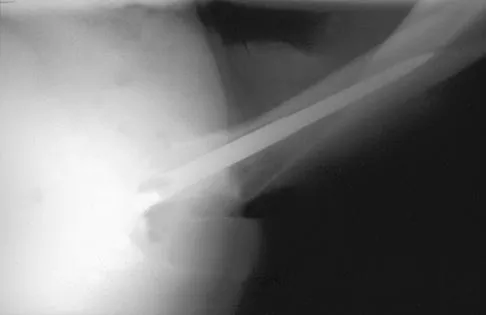

A 32-year-old woman sustained an injury to her left upper extremity in a motor vehicle accident. Examination reveals a 2-cm wound in the mid portion of the dorsal surface of the upper arm and deformities at the elbow and forearm; there are no other injuries. Her vital signs are stable, and she has a base deficit of minus 1 and a lactate level of less than 2. Radiographs are shown in Figures 9a and 9b. In addition to urgent debridement of the humeral shaft fracture, management should include

Explanation

With a severe injury to the upper extremity, the best opportunity for achieving a good functional result for a floating elbow is immediate debridement of the open fracture, followed by internal fixation of the fractures. The ability to do this depends on the patient's physiologic status. In this patient, the procedure is acceptable because she has normal vital signs and no chest or abdominal injuries, and normal physiologic parameters (base excess and lactate) show adequate peripheral perfusion. The surgical approaches will be determined by the associated injury patterns and open wounds. In this patient, the humerus was debrided and stabilized through a posterior approach as was the medial condyle fracture. The ulna was fixed through an extension of the posterior incision and the radius through a separate dorsal approach. Solomon HB, Zadnik M, Eglseder WA: A review of outcomes in 18 patients with floating elbow. J Orthop Trauma 2003;17:563-570.